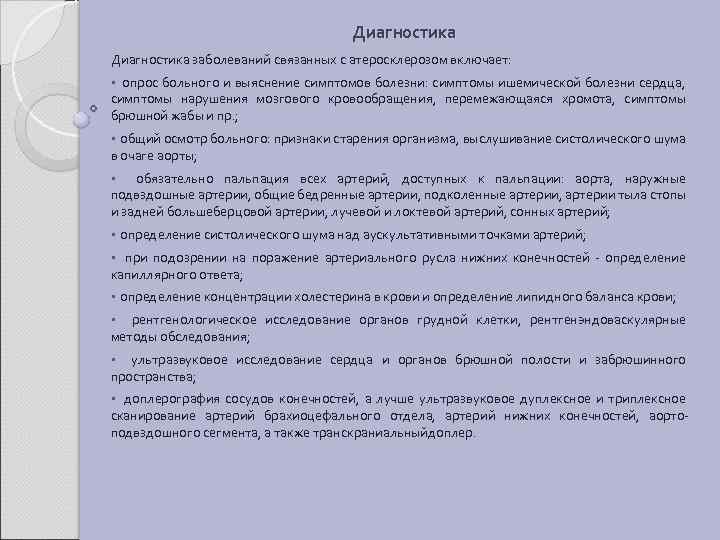

Диагностика заболеваний связанных с атеросклерозом включает: • опрос больного и выяснение симптомов болезни: симптомы ишемической болезни сердца, симптомы нарушения мозгового кровообращения, перемежающаяся хромота, симптомы брюшной жабы и пр. ; • общий осмотр больного: признаки старения организма, выслушивание систолического шума в очаге аорты; • обязательно пальпация всех артерий, доступных к пальпации: аорта, наружные подвздошные артерии, общие бедренные артерии, подколенные артерии, артерии тыла стопы и задней большеберцовой артерии, лучевой и локтевой артерий, сонных артерий; • определение систолического шума над аускультативными точками артерий; • при подозрении на поражение артериального русла нижних конечностей - определение капиллярного ответа; • определение концентрации холестерина в крови и определение липидного баланса крови; • рентгенологическое исследование органов грудной клетки, рентгенэндоваскулярные методы обследования; • ультразвуковое исследование сердца и органов брюшной полости и забрюшинного пространства; • доплерография сосудов конечностей, а лучше ультразвуковое дуплексное и триплексное сканирование артерий брахиоцефального отдела, артерий нижних конечностей, аортоподвздошного сегмента, а также транскраниальныйдоплер.